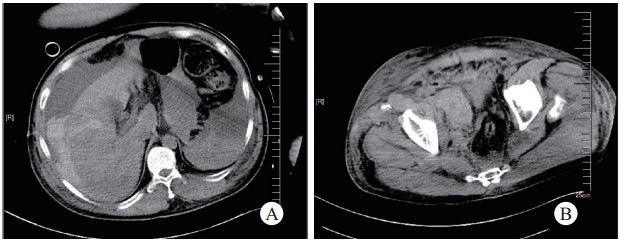

心率121次/min,血压114/82 mmHg,气管插管,腹部明显膨隆(膀胱内压50 cmH2O),全身多处皮肤淤青。血气提示乳酸14.5 mmol/L,pH 7.24, 血红蛋白8.5 g/L,钾6.5 mmol/L;血常规:WBC 10.88×109/L、NEUT 9.33×109/L、HGB 91 g/L、PLT 70×109/L;肝肾功:Cr 209 μmol/L、ALT 159 U/L、AST 347 U/L。医院立即组织相关科室MDT会诊。急诊增强CT提示:右侧第6肋骨线性骨折、肺挫伤、肝脏破裂(图 4A)、盆腔右侧血肿(图 4B)、双侧耻骨上下支骨折,右侧髂骨、右侧髋臼前份、骶骨右侧骨折。

| 图 4 2019年6月18日19时CT提示肝破裂(A)、骨盆骨折、髂窝血肿(B) |